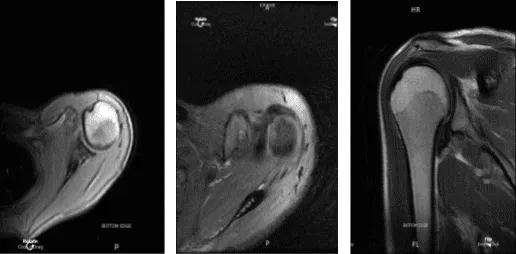

La paciente es una chica de 29 años que vino a verme tras sufrir un accidente de coche y quejarse de un dolor en la parte anterior del hombro en el lado izquierdo. La fisioterapia y los antiinflamatorios resultaron ineficaces. Realizamos una resonancia magnética, que reveló una rotura del labrum tipo 2.

Resonancia magnética Hombro izquierdo sin contraste